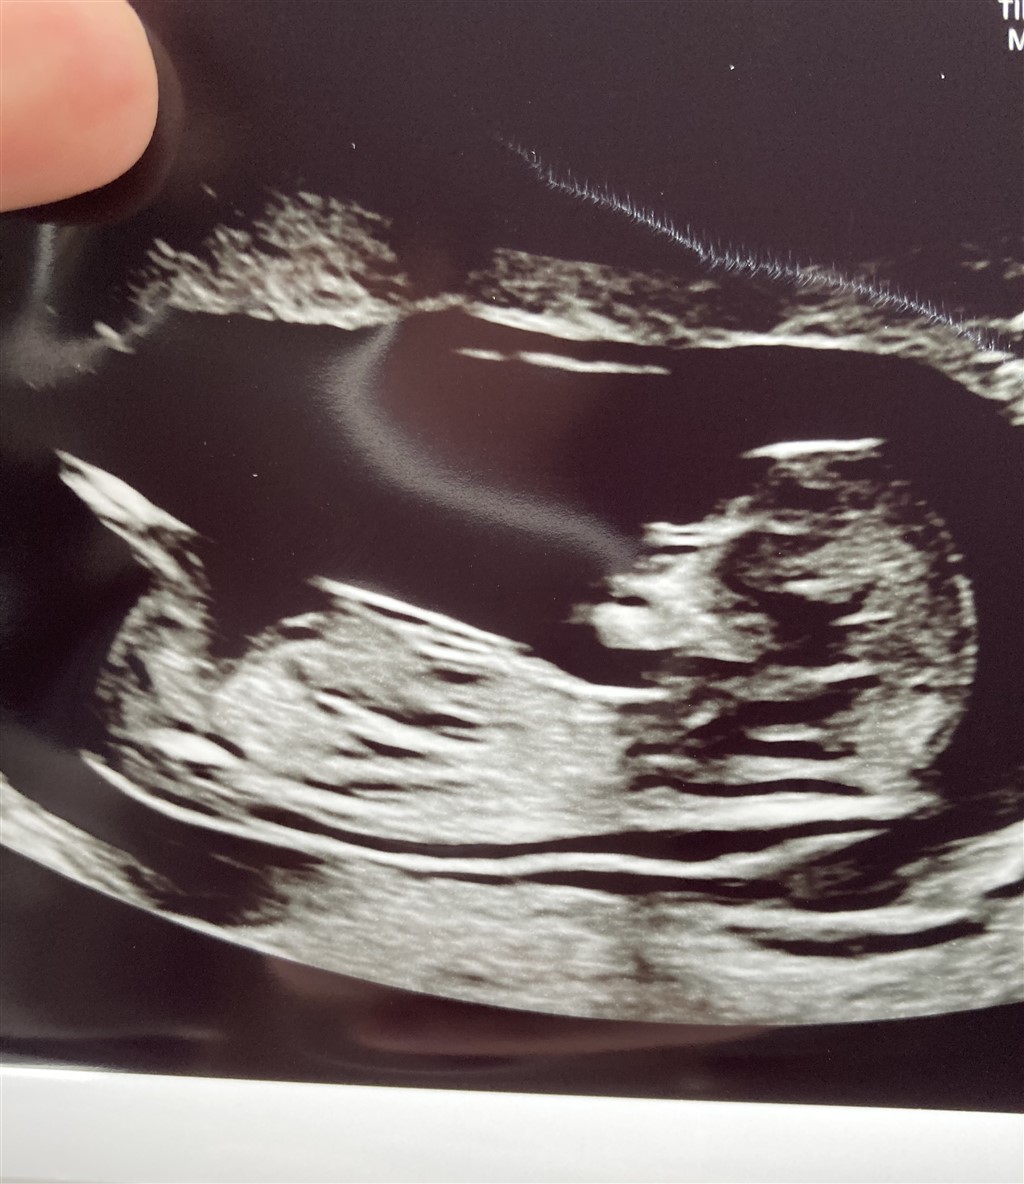

Ja så er der endnu en baby på vej. Bestemt ikke planlagt og lavet trods udebleven mens, men til verden dét vil den. Så velkommen det er den i hvertfald

Har været til nf som gik rigtig godt og måler baby til 12+5

Nogle gæt til hvad det kunne udvikle sig til?